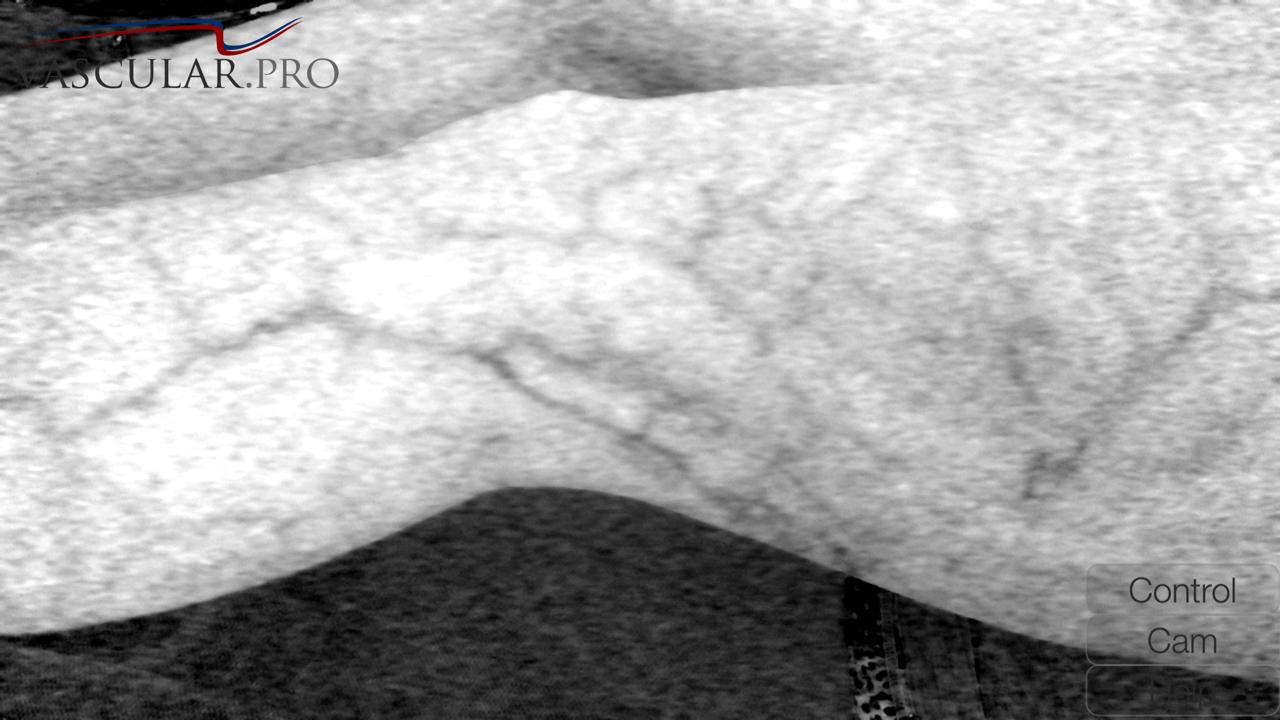

Varizes com Espuma Densa (Tratamento de varizes, tecnica vascular)

Dr Alexandre Amato (CRM 108651) explica o que é a espuma densa no tratamento de varizes e qual é a situação dessa técnica perante outras… Read More »Varizes com Espuma Densa (Tratamento de varizes, tecnica vascular)